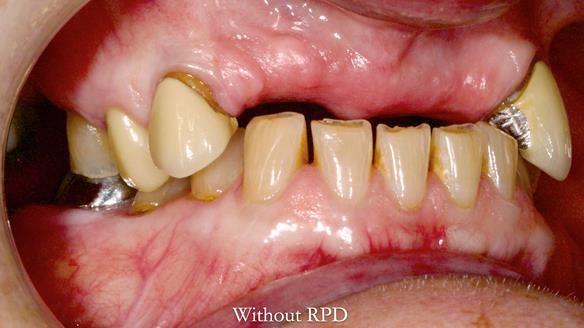

This is one of those cases that reminds me why I love removable prosthodontics. Pam was an absolute joy to treat — we were on the same page throughout. Her old upper flexible denture was loose, uncomfortable, and unaesthetic. We replaced it with a carefully designed metal-based upper partial denture/splint and new porcelain-bonded-to-zirconia (PBZ) crowns for the canines. The result is stable, comfortable, and natural-looking.

- Diagnosis and plan – Flexible upper denture ill-fitting with poor stability, retention, and appearance. Plan: metal-based upper partial denture/splint with lighter porcelain-bonded-to-zirconia crowns on UR3 and UL3.

- Metalwork framework try-in – to verify fit, path of insertion, and support.